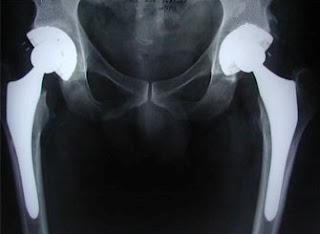

This man has two hip replacements. And he can get down better than you. His pelvis x-ray probably looks a little something like this: